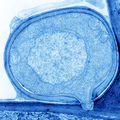

ABOUT THIS IMAGE

A Germinated Microsporidian Spore in Close Proximity to the Host Cell Surface

Transmission electron micrograph shows a germinated microsporidian spore adjacent to a host cell, with a polar tube extending to transfer sporoplasm into the host cytoplasm. The study identified EnP1, a nucleus-targeted effector secreted by microsporidia, which enhances their proliferation by interacting with host histone H2A and inhibiting ferroptosis. This research highlights how microsporidia alter host cell functions through secreted effector proteins, ultimately facilitating their own survival and contributing to disease progression. Guan et al. 2026

Image Credit: Bing Han